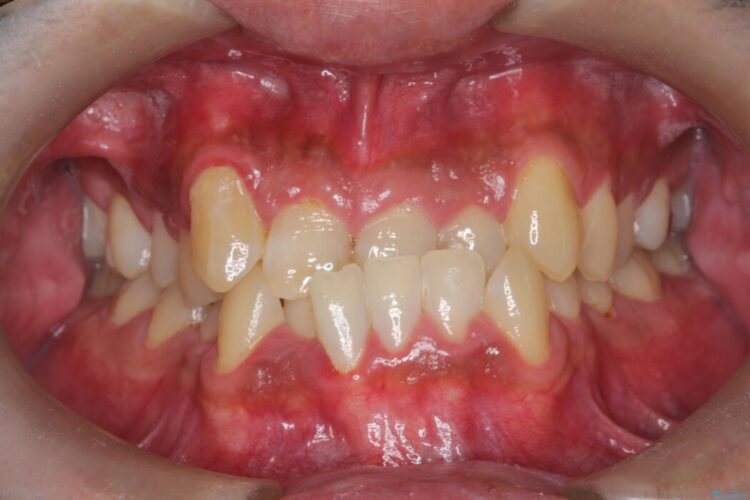

反対になっている嚙み合わせを改善したいとご来院されました。

診査の結果、上下左右4番の歯を抜歯し、審美装置にて反対咬合と叢生を改善していくこととしました。

骨格性Ⅲ級を示しましたが、構成咬合位がとれたことから反対咬合と叢生改善のため、上下左右第一小臼歯を抜歯しワイヤー矯正を行いました。途中、バイトアップを行っています。